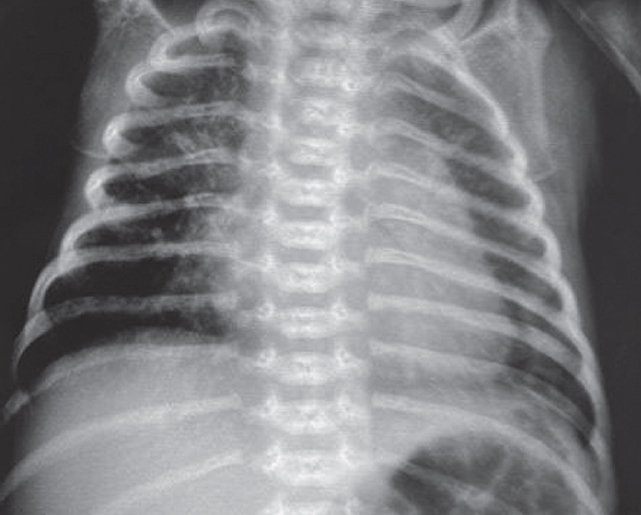

The article presents a case of successful treatment of acute respiratory distress syndrome in a full-term newborn complicated by pulmonary barotrauma using monobronchial administration of exogenous surfactant under X-ray control. In order to assess the course of the disease and the effectiveness of treatment, a retrospective analysis of medical documentation was carried out. From the first minutes of life, the child had respiratory disorders, which was the basis for non-invasive mechanical lung ventilation — nCPAP (nasal continuous positive airway pressure). Progression of hypercapnia and hypoxemia was revealed over time, and therefore tracheal intubation was performed and convective mechanical ventilation was started with FiO2 = 1,0. Monobronchial administration of exogenous surfactant was a key element of the therapy that allowed to achieve stabilization of the condition and regression of gas exchange disorders with complete recovery of the patient.